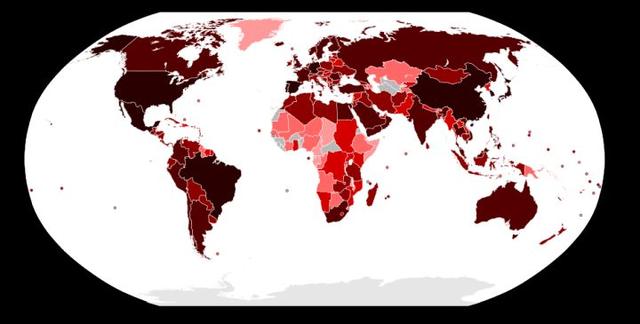

感染人口比_60岁以上人口占比图(2)

6000万人感染 1.2万人死亡 对比美国大流感,才知道中国有多难

美国单日新增新冠肺炎确诊超22万例,累计超1737万例

印度疫情失控,首都一半人口已感染新冠,早已实现 群体免疫

4个月1500万人感染,超过8000人死亡,流感大灾横扫美国

血清调查发现 印度超过6300万人感染新冠病毒